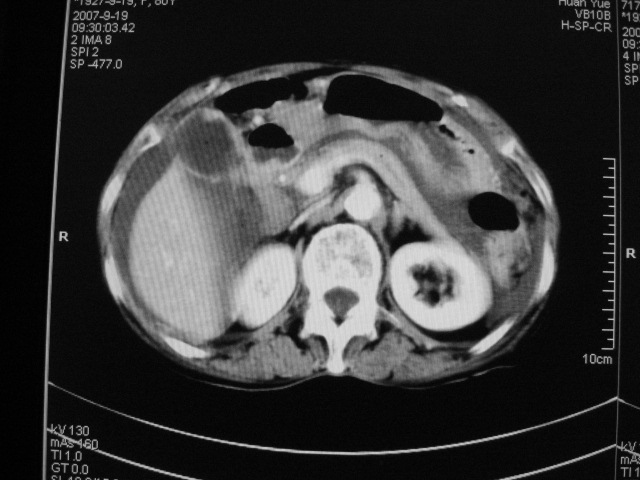

以下是引用zjzjr在2007-9-20 19:15:00的发言:[br]慢性胆囊炎伴炎性息肉可能性大.腹水.

以下是引用默契在2007-9-20 17:29:00的发言:[br][br] [br] 考虑:1、胆囊占位性病变(以癌可能性大);[br] 2、中量腹水。 [br] [br]

以下是引用快乐男生在2007-9-20 15:32:00的发言:[br]图像质量不好:[br]胆囊增大,囊壁增厚,[br]可见结节突出囊腔内,[br]增强后与囊壁相仿.[br]考虑多为胆囊慢性炎症伴有胆囊体部的息肉